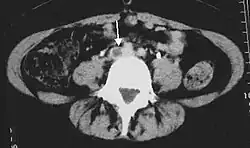

An ultrasound with a blood clot visible in the left common femoral vein. (The common femoral vein is distal to the external iliac vein.)

Compression ultrasonography for suspected deep vein thrombosis is the standard diagnostic method, and it is highly sensitive for detecting an initial DVT.[13] A compression ultrasound is considered positive when the vein walls of normally compressible veins do not collapse under gentle pressure.[19] Clot visualization is sometimes possible, but is not required.[82] Three compression ultrasound scanning techniques can be used, with two of the three methods requiring a second ultrasound some days later to rule out the diagnosis.[13] Whole-leg ultrasound is the option that does not require a repeat ultrasound,[13] but proximal compression ultrasound is frequently used because distal DVT is only rarely clinically significant.[9] Ultrasound methods including duplex and color flow Doppler can be used to further characterize the clot[9] and Doppler ultrasound is especially helpful in the non-compressible iliac veins.[82]